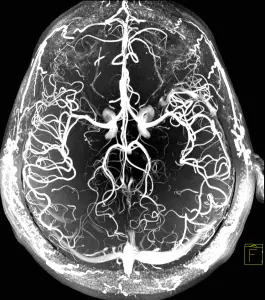

Малюнок – МРТ судин шиї та голови.

МРТ реконструкція судин голови і шиї дозволяє виявити слабкі місця в кровопостачанні мозку. Іншими словами – ділянки мозку з дефіцитом кровопостачання через патологію судин. Як показує наша багаторічна практика, це може бути недорозвинення (звуження або повна відсутність) деяких судин у мозку. Наприклад, в задньому сегменті так званого судинного Віллізеєва кола (центр з’єднання декількох магістральних артерій в мозку), такі зміни зустрічаються у 24,5% людей. Ця цифра встановлена H.Yasargil (Німеччина) і приведена Piter Duus в 1997.

Віллізеєве судинне коло – це місце злиття чотирьох головних артерій головного мозку. Така будова судин мозку була передбачена природою для підстраховки: якщо одна артерія виходить з ладу (частіше на шиї), то кровотік компенсується за рахунок інших трьох артерій.

Для розуміння причини запаморочення або головного болю важливо побачити ті судини, які звужені або які зовсім не працюють. Як було сказано вище, мозок харчується чотирма великими артеріями. Ці судини проходять через шию, входять в порожнину черепа і утворюють Веллізеєве коло і далі судини починають галузиться.

На МРТ видно не тільки великі, але більш дрібні артерії мозку.

Можна побачити відсутність (нерозвиненість) або звуження (недорозвинення, спазм) однієї з артерій. Такі зміни в судинах можуть викликати збій функції ділянки мозку. У тому числі ділянки, від якої залежить запаморочення або головний біль.

Зображення судин при МРТ виходить за рахунок оцінки апаратом руху крові в судині. Принцип МРТ діагностики – це оцінка різних фізичних станів рідини. Кров – це рухома рідина з іншими фізичними характеристиками, ніж тканини мозку. Тому за допомогою МРТ ми можемо оцінити не тільки стан мозку, а й стан судин. Спеціальні програми МРТ апарату «ловлять» потік крові в судинах, запам’ятовують цей сигнал і передають інформацію в свій МРТ-комп’ютер. Там інформація обробляється і виводиться на екран у вигляді зображення мережі всіх судин мозку (див. нижче).

Отримане зображення – тривимірне. Його можна покрутити за допомогою мишки в трьох площинах і, таким чином, простежити хід будь-якої судини головного мозку. Судину видно на всьому своєму протязі. У неї можна виявити звуження (спазм, атеросклероз, недорозвинення) або розширення (аневризма).